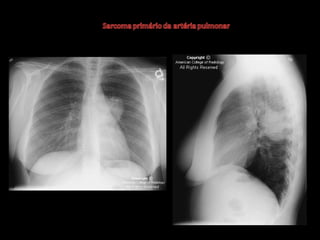

Exames de imagem: Rx Tórax

Primeiro passo na investigação radiológica da

suspeita de HAP;

Achados típicos: aumento do calibre das artérias

centrais, com rápido afilamento dos vasos à medida

que progridem para a periferia;

A área cardíaca pode estar aumentada ou normal;

Calcificação vascular: associado a alta RVP;

Sensibilidade baixa;

Útil para afastar ou sugerir causas de HAP;

Radiografia de tórax normal